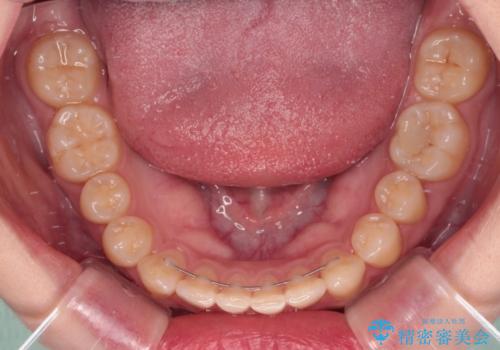

治療途中の奥歯と矯正治療の後戻り インビザライン・ライトによる矯正治療

- 根管治療を行ったままの奥歯と、矯正治療の後戻りを気にして来院された患者様です。

根管治療された歯に症状はなく、オールセラミッククラウンにて補綴治療を行うこととしました。

矯正治療の後戻りは軽微であったため、インビザラインの簡易パッケージであるインビザライン・ライトを用いて歯列を整えることとしました。

クラウンはよりよい咬み合わせで装着したいため、インビザラインを1セット使用して概ね歯列を整えた時点で補綴治療を行い、その後仕上げの矯正治療を行いました。